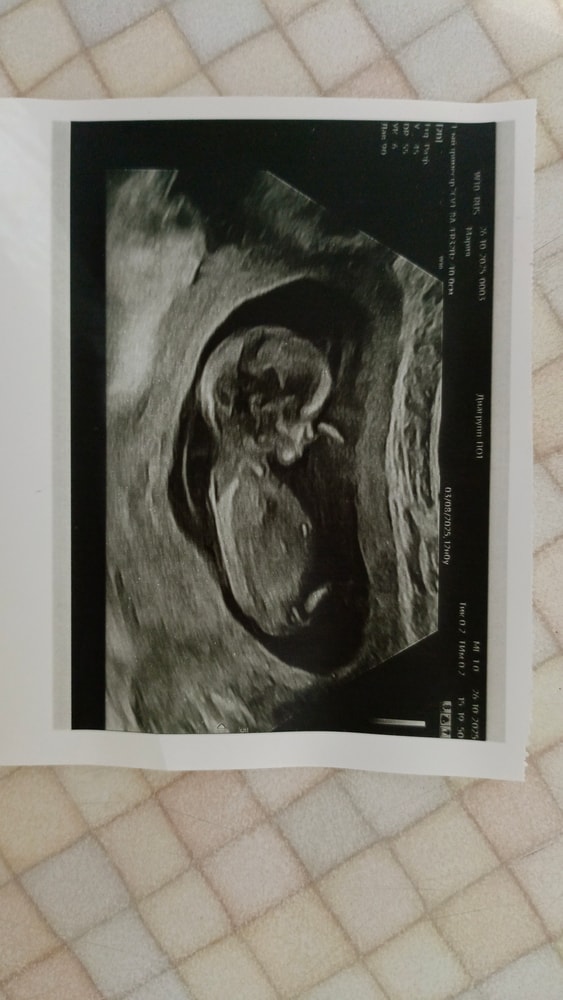

На кого похож?

Девочка

На девочку.